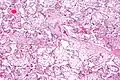

| Micrograph of villous immaturity. H&E stain. | |

Placental villous immaturity is chorionic villous development that is inappropriate for the gestational age.

Immature chorionic villi are larger and have more central blood vessels; thus, the diffusion distance for gas and nutrient exchange is larger and, therefore, placental function is impaired.

Low mag.